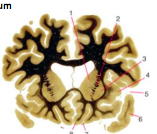

Huntington’s Disease

Loss of volume of Caudate Nucleo, enlargement of frontal horns

Enlargement of subarachnoid space, frontal convexity, interhemispheric scissure, sylvian region, and choroid fissures